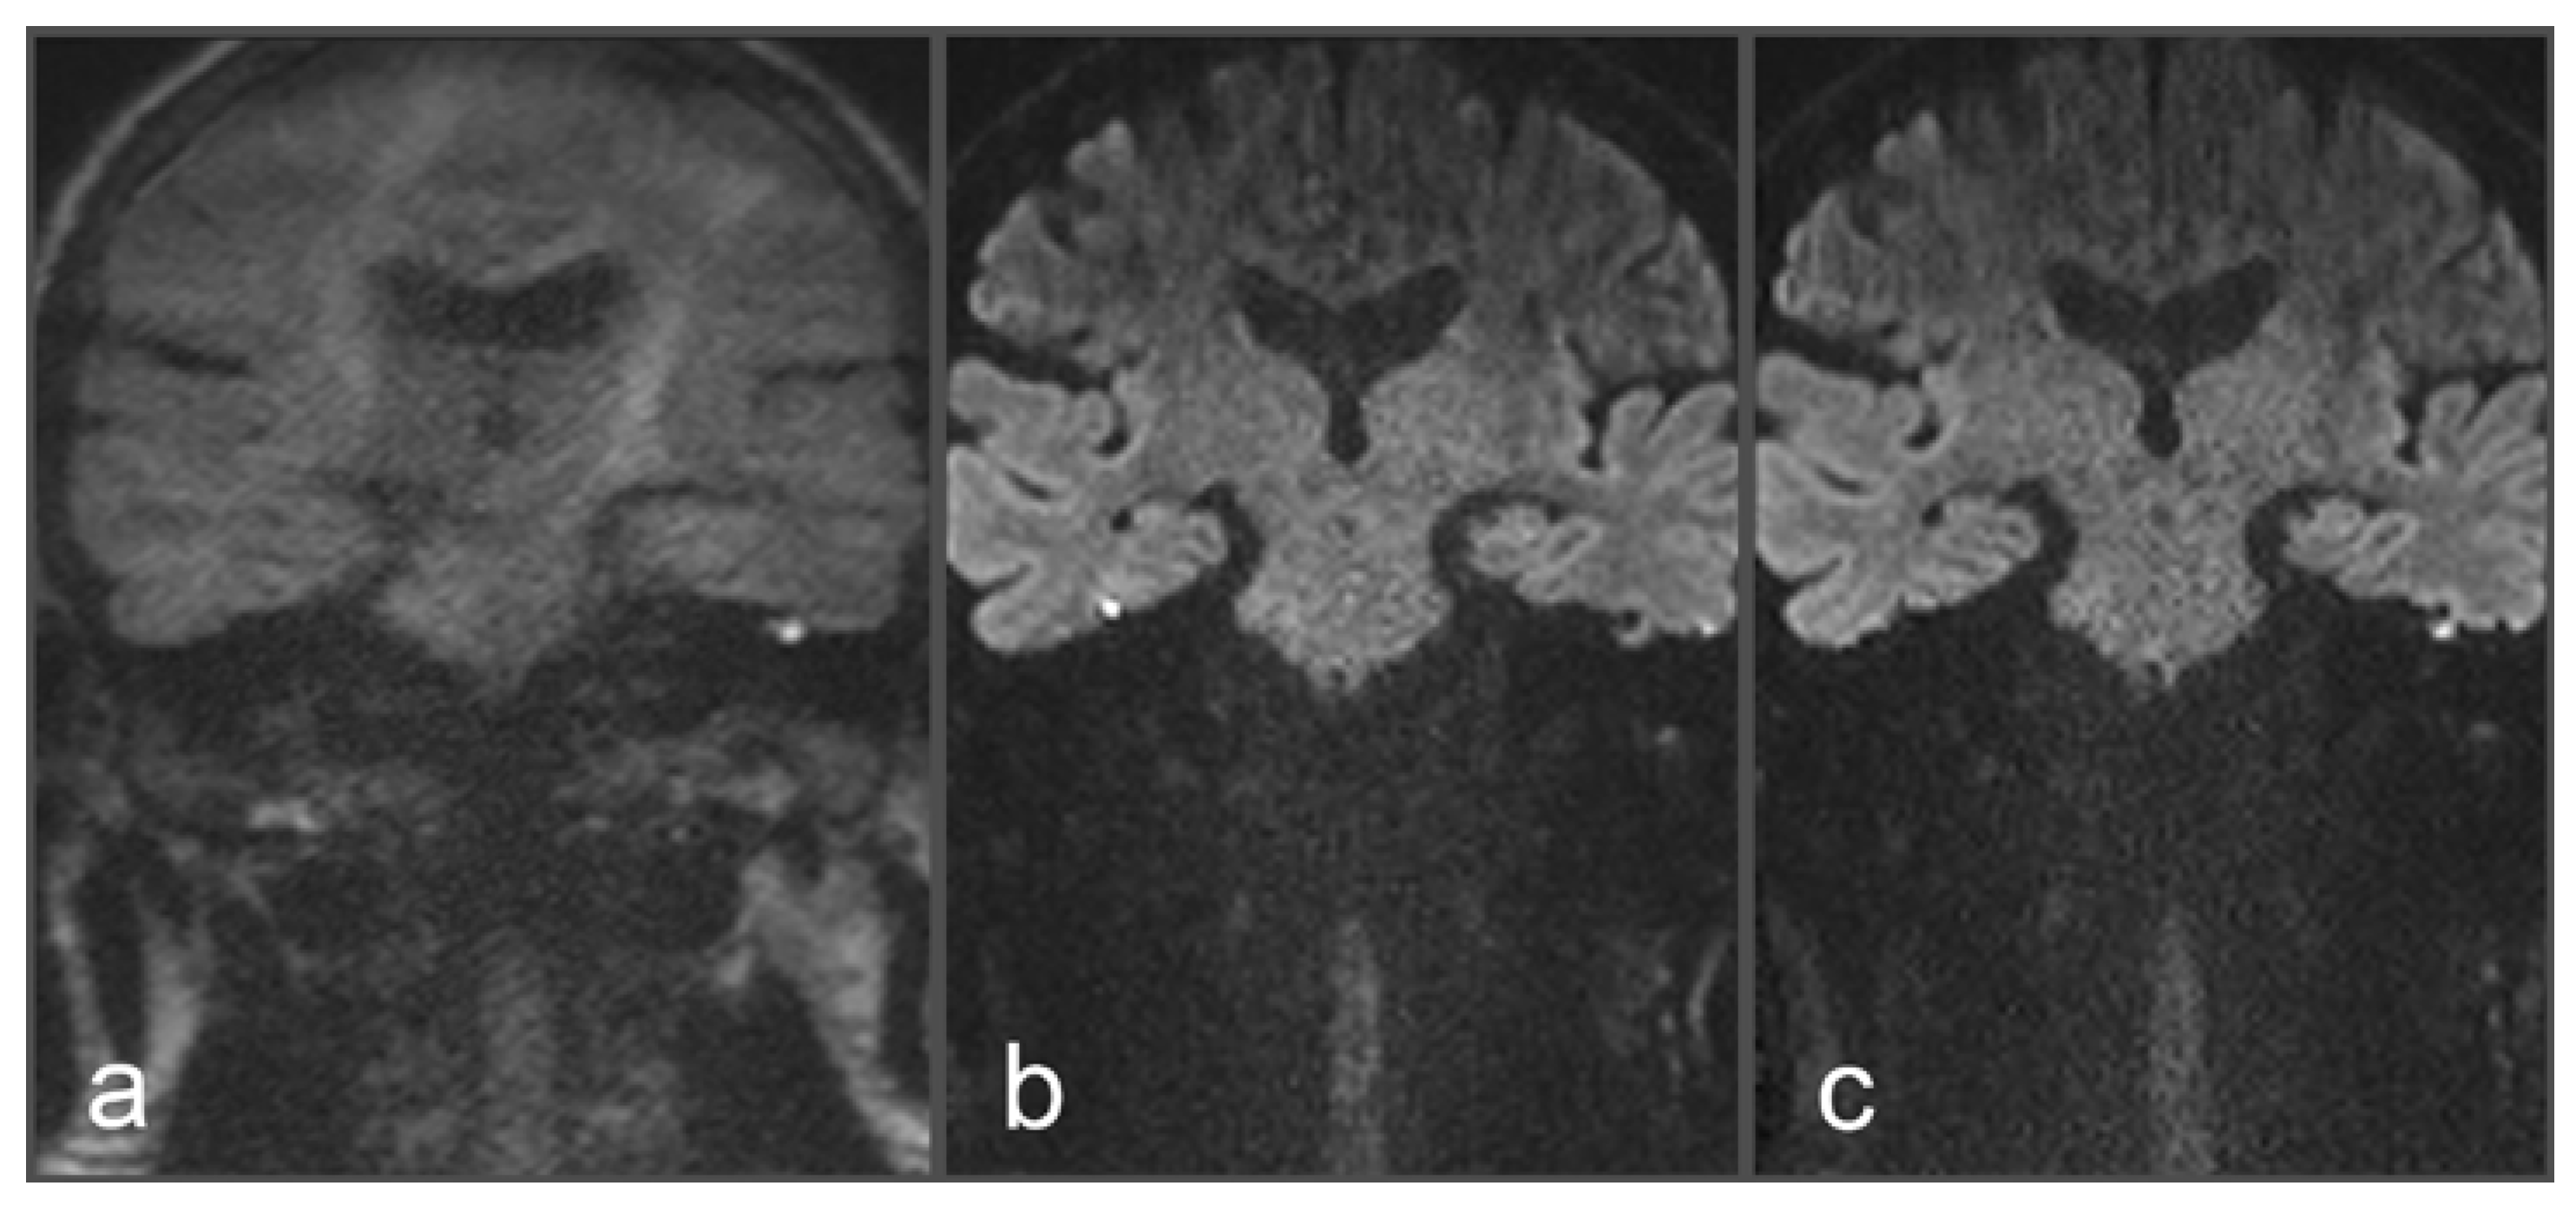

Figure 3. Images of a 54-year-old patient with a suspected cholesteatoma on the right side. (a) and (d) tseDWI (axial and coronal slice orientation). (b) and (e) uncorrected rsDWI (axial and coronal slice orientation). (c) and (f) top-up-corrected rsDWI (axial and coronal slice orientation). tseDWI images show an elongated hyperintense middle-ear lesion on the right side, which could be confirmed as a cholesteatoma after histopathological examination. The lesion is hardly visible in both uncorrected rsDWI images (especially on the axial images) and exhibits a geometrical distortion with a bent-like appearance on both slice orientations. Additionally, two punctiform hyperintensities are visible on both sides at the height of the temporal cortex. Both hyperintensities are missing on the tseDWI and the topup-corrected rsDWI images, strongly indicating that these hyperintensities represent artifacts. On the topup-corrected rsDWI images, the cholesteatoma on the right side exhibits a better contrast compared to uncorrected rsDWI, and geometrical distortions are comparably minor. Additionally, topup-corrected rsDWI does not show the above-described likely false-positive lesions at the border zone between bone and brain tissue.